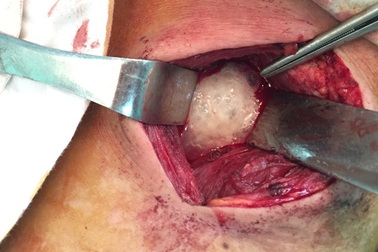

Cứu sống 1 bệnh nhân bị áp xe trung thất do thủng thực quảnNgày 27/7, tin từ Bệnh viện Trung ương Huế cho biết vừa tiến hành phẫu thuật cứu sống nữ bệnh nhân Đặng Thị H. (31 tuổi) bị thủng thực quản sau hóc xương gà gây biến chứng áp xe trung thất lan rộng.